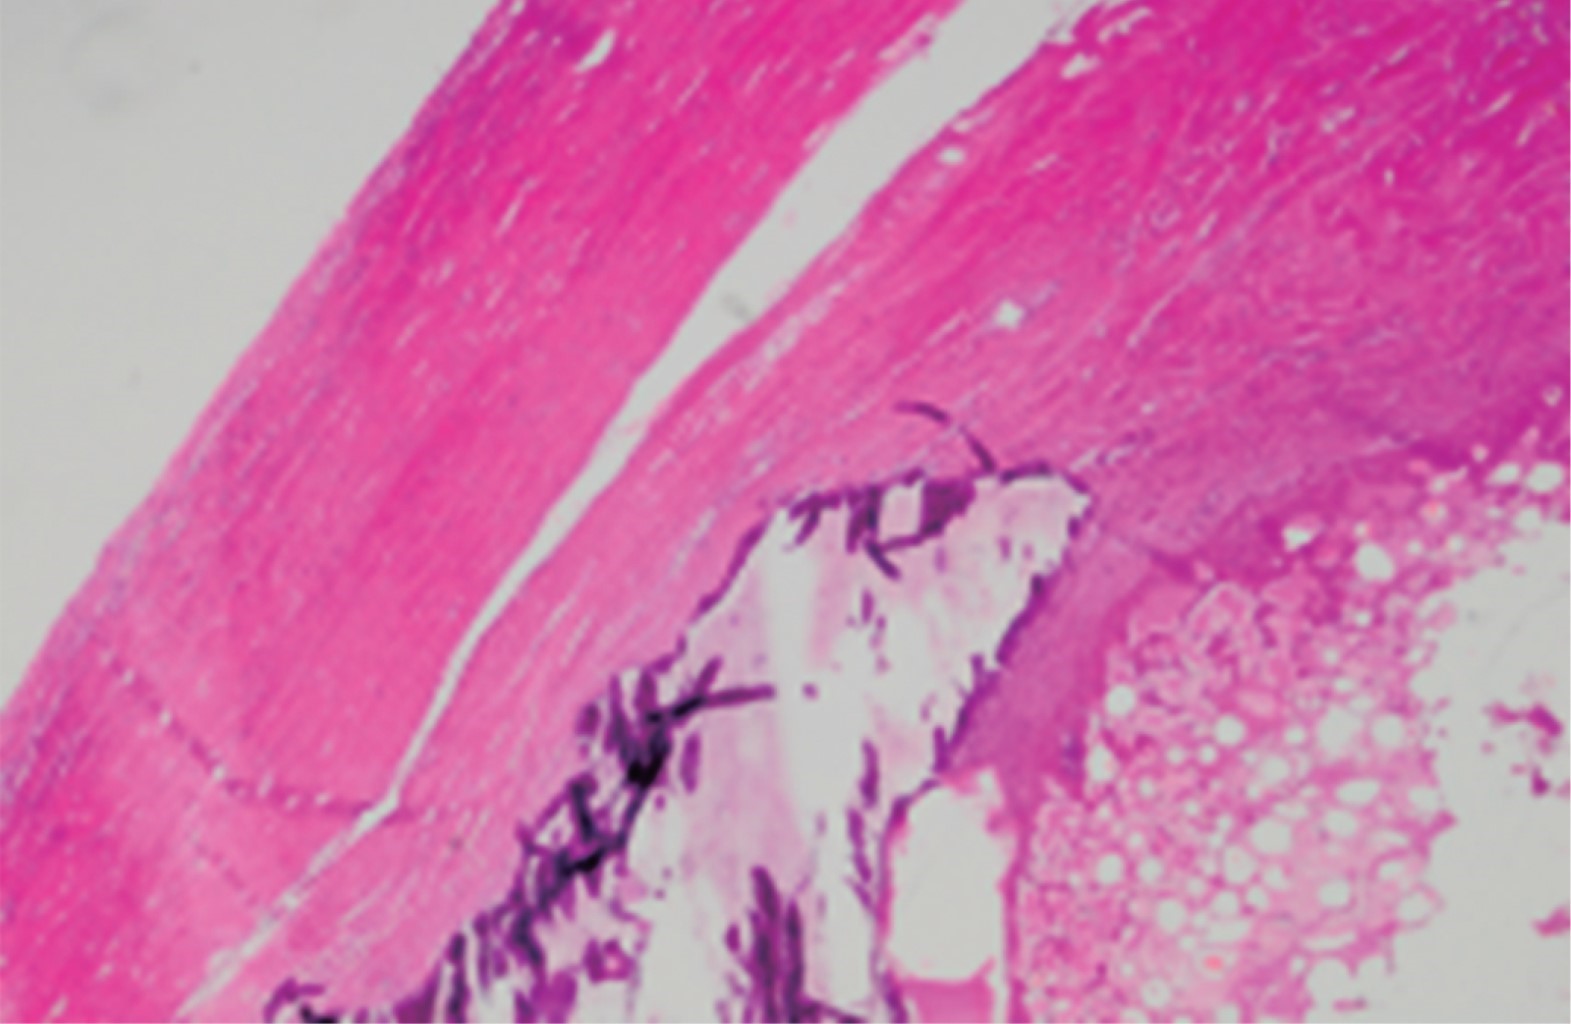

Microscopic description consists of epiploic appendices with dense connective tissue at the periphery, with dystrophic calcification and areas of fat necrosis, without other alterations or histological changes of malignant neoplastic type. Final diagnosis was of an acute fibrinopurulent appendicitis (Figure 5).

Figure 5